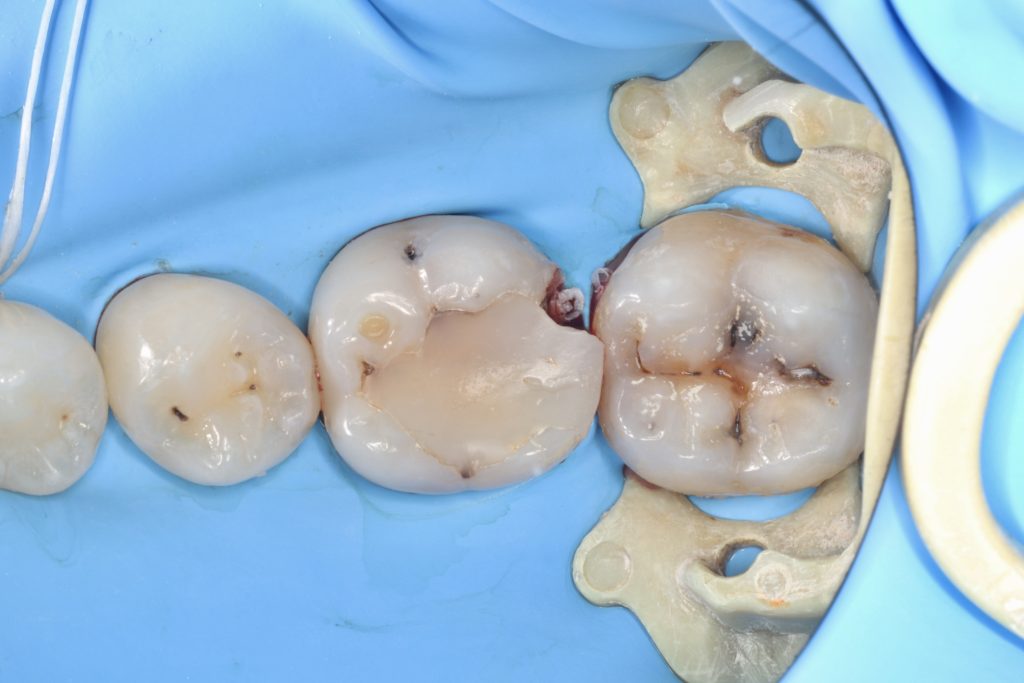

3.6 in-direct resin ceramic

3.7 direct composite

3.6 is not recommended for direct restoration due to the thickness of the cusps.

The crack line can be seen in 25x magnification videos.

The patient did not experience any spontaneous pain in the mandibular first molar cavity

The pulp vessel structure’s health at 25x magnification led to its closure with MTA.